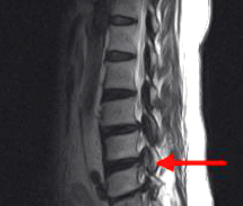

척추협착증 진단

척추협착증 진단, CT와 MRI 촬영 등을 통해서 척추관 크기와 주변 관절과 인대, 추간판의 상태를 알아보고 종합적으로 진단을 하게 됩니다. 근전도 검사와 신경전도 검사도 함께 병행해서 하게 되겠습니다.